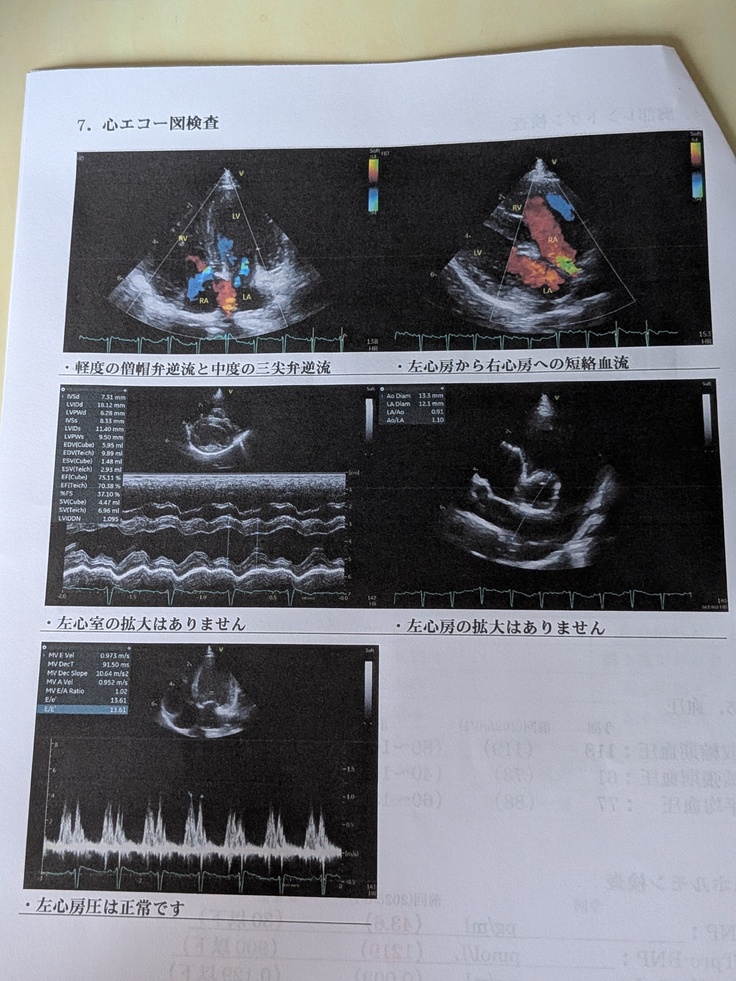

今回もとっても順調✨✨若干、前回より右心室の拡大は見られるものの、問題ない範囲とのこと😌

その他、継続的に三尖弁の逆流は見られるものの、問題なし‼️

※病院の報告写真と“すあま”の写真を掲載します✨